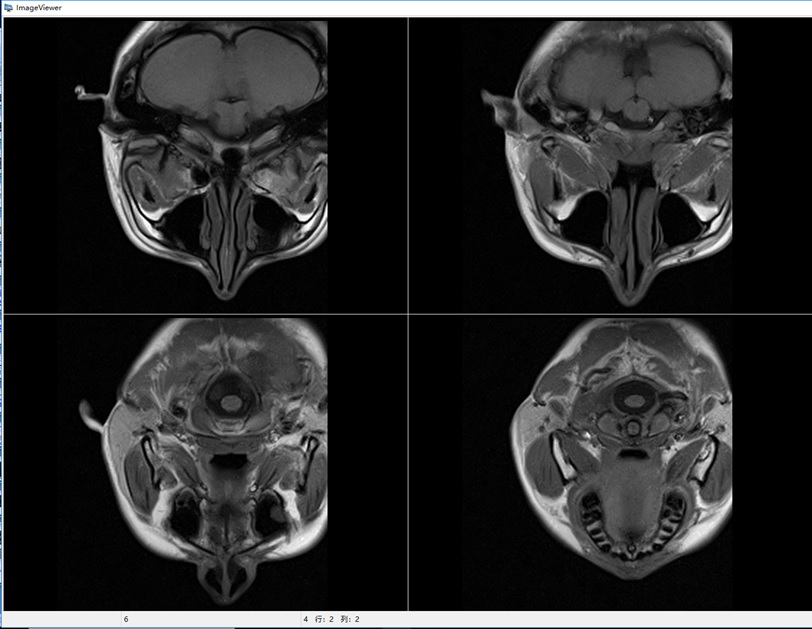

移動式POCI磁共振成像儀屬于POCI(point of care imaging)成像裝備,也就是即時監護成像,包括但不限于:神經內科和神經外科的腦監護成像、新生兒腦監護、口腔醫學以及運動損傷監護等,主要用于各類相關臨床醫院、科研機構、研究型醫院,用于臨床診斷和疾病的動物模型研究、認知研究、新藥研發等。我們研發的移動式POCI磁共振成像儀,采用了最新的輕量化永磁磁體技術和高效率的矩陣梯度技術,使得整機具有更高的磁場強度、更低的使用成本、更好的成像效果和適用性。目前國內MRI裝機量超過了11000臺,而移動式POCI磁共振成像儀目前國內外還沒有成熟的產品。預計將來移動式POCI磁共振成像儀的需求量接近全身MRI設備的需求,其總市場價值約有150億元,因此移動式POCI磁共振成像儀具有良好的市場前景和經濟效益。